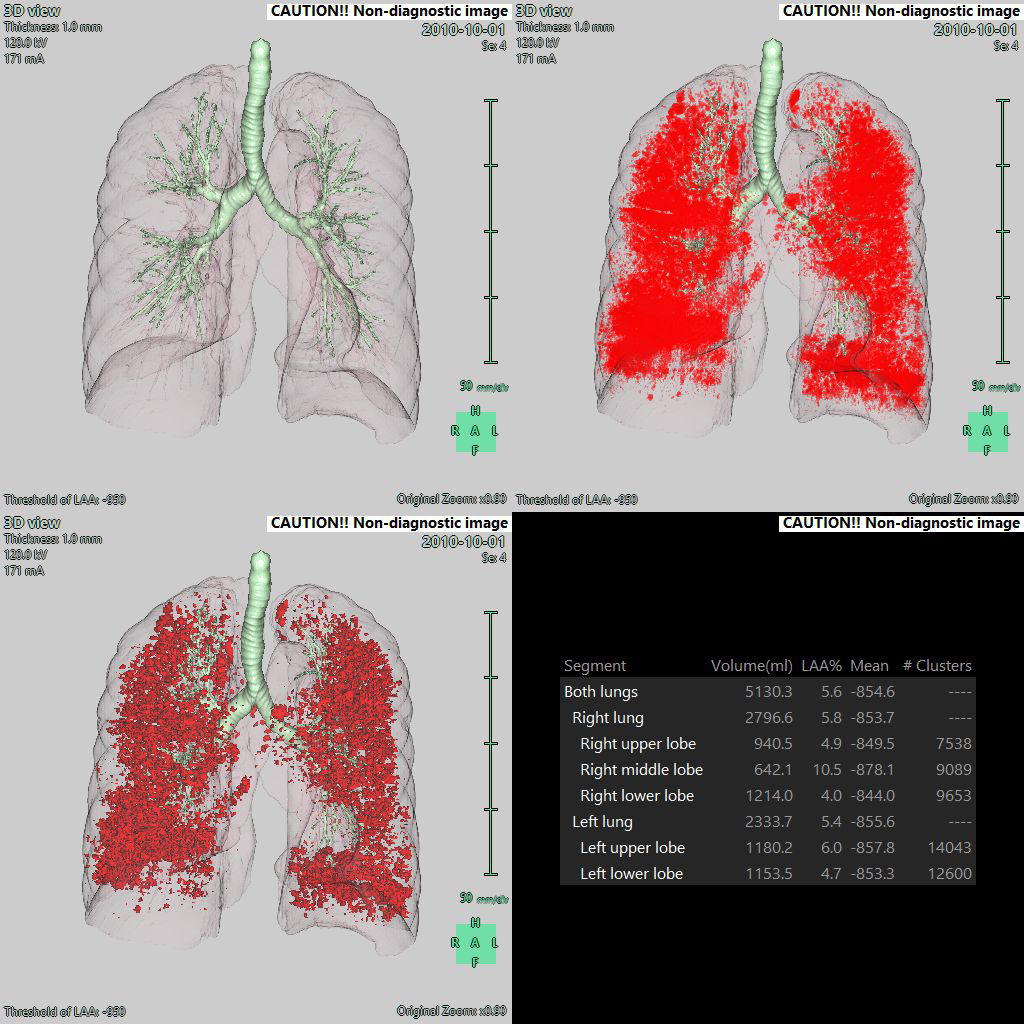

• - CT image에서 Airway, Lung field의 Low attenuation area를 분석할 수 있습니다.

• - 분리한 각 영역에서의 LAA region의 volume, rate 및 mean CT value를 측정할 수 있습니다.

• - LAA region의 군집도를 시각화하여 평가할 수 있습니다.

LAA View

Cluster View